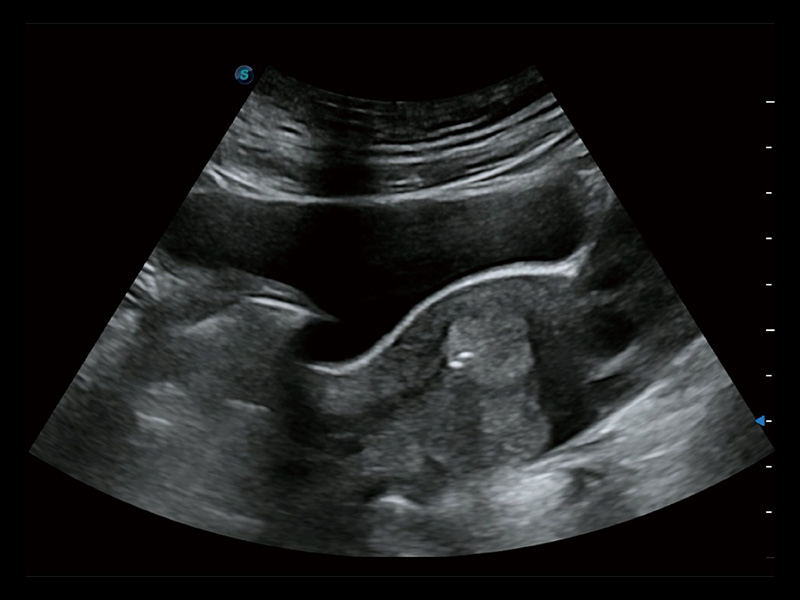

“生育问题”即关系民族复兴,也关系亿万家庭的幸福。随着婚育年龄推迟、社会压力增加等因素,越来越多人群也面临着“生不出、生不好”的问题。辅助生殖作为治疗不孕不育最有效的方法之一,也逐渐成为育儿新希望。而超声检查能为生殖需求人群的初诊评估提供宝贵的信息。 P20 Elite是开立医疗匠心打造的一款生殖应用型彩超。她继承开立医疗高端极光平台,突破性地将多款新型芯片及硬件模块进行整合,均衡了高端系统性能与小巧灵动机身。P20 Elite卓越的图像质量搭载专科探头,旨在为您提供全面的辅助生殖解决方案。

P20 Elite配备了丰富的生殖探头群和临床应用功能,在卵泡监测、穿刺取卵、胚胎移植、妊娠确认等领域,为生殖需求人群提供了新的临床机会,重新定义高端超声如何应用于生殖健康检查。